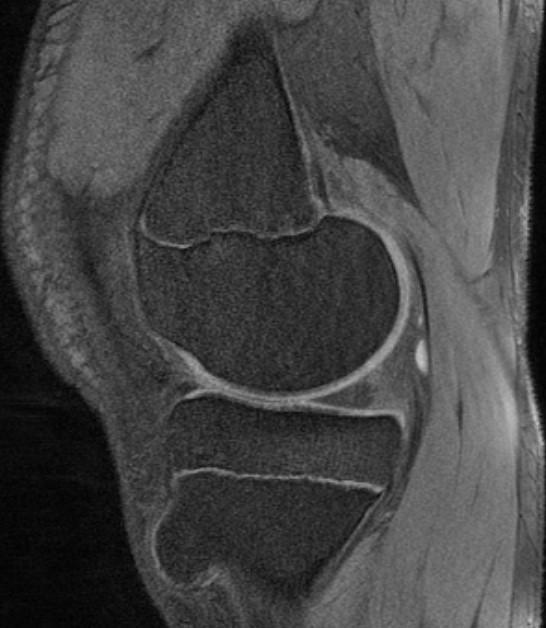

*13-year-old boy with mass on the proximal tibia.

Answer: Osteochondroma

MR images show osteochondroma on the proximal tibia.

They can be either pedunculated or sessile, and are seen in the metaphyseal region typically projecting away from the epiphysis on plain film.

MRI is the best imaging procedure to evaluate cartilage thickness, presence of edema in bone or adjacent soft tissues, and visualizing neurovascular structures in the vicinity.

The cartilage cap appears the same as cartilage elsewhere, with intermediate to low signal on T1WI and high signal on T2WI. The cartilage cap of over 1.5 cm in thickness is suspicious for malignant degeneration. The cartilaginous cap itself should not enhance.